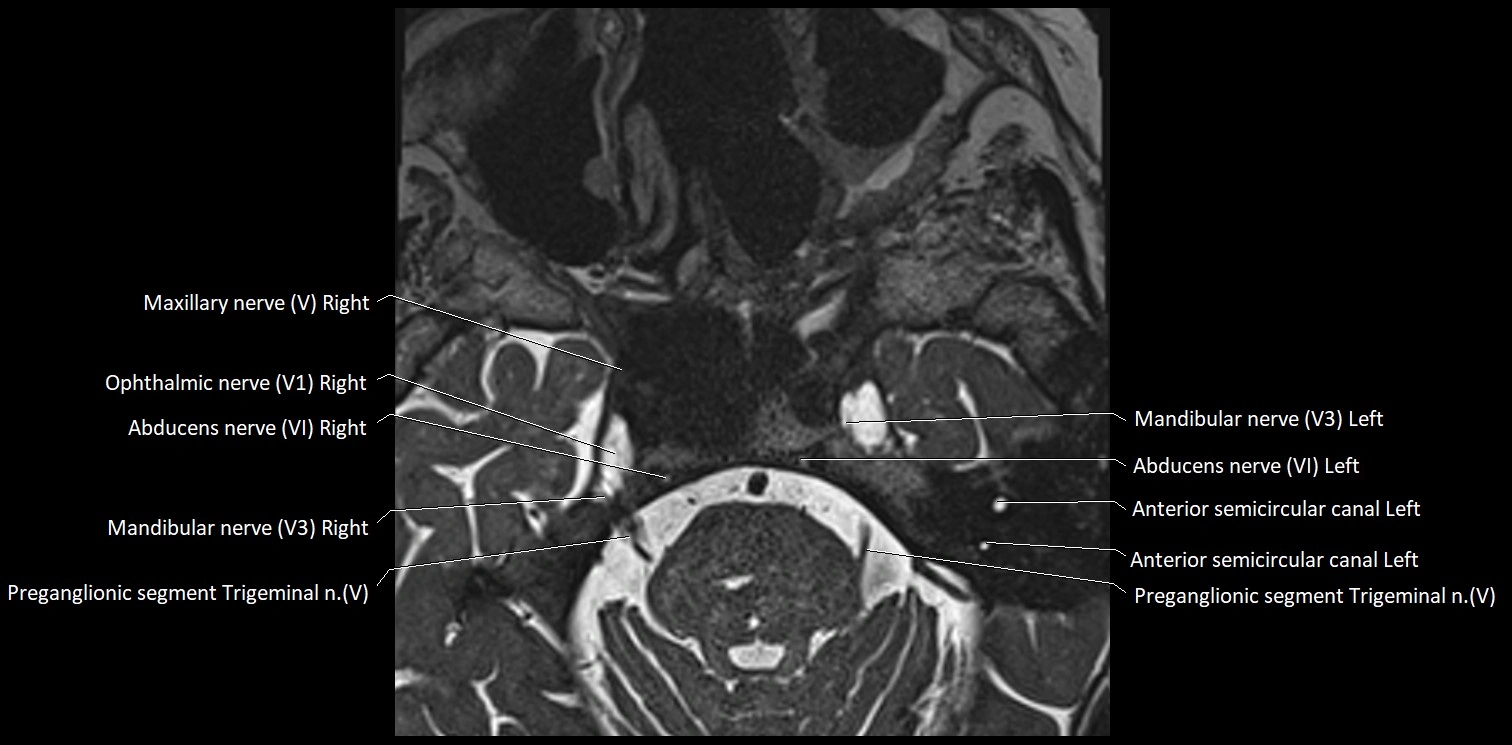

MRI Appearance

• The abducens nerve is a small, thin, linear structure

• Best visualized on high-resolution T2-weighted 3D MRI sequences (e.g., FIESTA or CISS)

• Seen as a hypointense (dark) line running from the brainstem at the pontomedullary junction, traversing the prepontine cistern, and entering Dorello’s canal under the petrosphenoidal ligament, then into the cavernous sinus, and finally the orbit

• May be challenging to visualize in standard MRI due to its small size

• Pathology may be inferred by absence, displacement, or enhancement of the nerve

MRI images

image